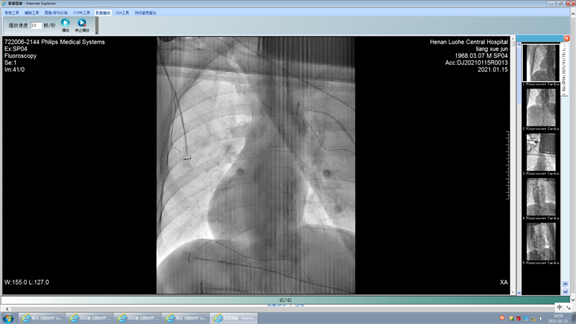

发作时心电图逆时针90度

电生理团队术前和患者及家属充分沟通,并征得家属签字同意后,入院当日就在三维标测系统指导下行心内电生理检查及射频消融术。因患者心脏位于右侧胸腔,团队克服重重困难,重建右心房和右心室的三维模型。电生理检查提示,房室结折返性心动过速。